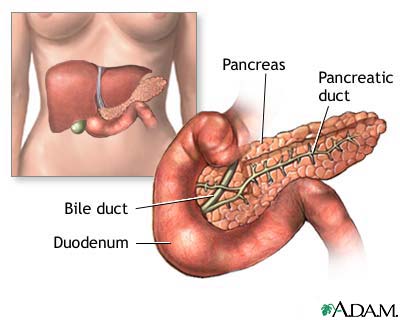

The formation of gallstones is a complex process that starts with bile, a fluid composed mostly of water, bile salts, lecithin (a type of phospholipid), and cholesterol. Most gallstones are formed from cholesterol.

- Bile is important for the digestion of fat. It is first produced by the liver and then secreted through tiny channels that eventually lead into a larger tube called the common bile duct, which leads to the small intestine.

- Only a small amount of bile drains directly into the small intestine, however. Most flows into the gallbladder through the

cystic duct

, which is a side branch off the common bile duct. This system of ducts through which bile flows is called thebiliary tree

- The gallbladder is a 3 to 4-inch (7 to 10 cm) sac with a muscular wall that is located under the liver. Here, most of the fluid is removed from the bile (about 2 to 5 cups, or 0.6 to 1.2 liters of bile gets produced by the liver in a day), leaving only a few tablespoons of concentrated bile.

Common bile duct stones are responsible for most cases of pancreatitis (inflammation of the pancreas), a condition that can be life-threatening. The pancreatic duct, which carries digestive enzymes, joins the common bile duct right before it enters the intestine. It is therefore not unusual for stones that pass through or lodge in the lower portion of the common bile duct to obstruct the pancreatic duct.